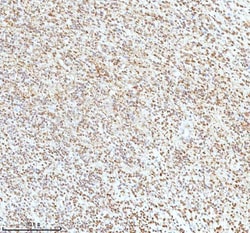

Reconstitute with 0.2 mL of distilled water to yield a concentration of 500 μg/mL. Positive Control - WB: human LNCAP whole cell, human Hela whole cell, human 293T whole cell, human HepG2 whole cell, human Jurkat whole cell, human K562 whole cell, human A549 whole cell, human A431 whole cell. IHC: human bladder cancer tissue, human bladder cancer tissue, human colon adenocarcinoma tissue, human colon adenocarcinoma tissue, human glioblastoma tissue, human glioblastoma tissue, human liver cancer tissue, human liver cancer tissue, human lung adenocarcinoma tissue, human lung adenocarcinoma tissue, human pancreas ductal adenocarcinoma tissue, human pancreas ductal adenocarcinoma tissue, human testicular seminoma tissue, human testicular seminoma tissue. ICC/IF: U2OS cell. Flow: A431 cell. Store at -20°C for one year from date of receipt. After reconstitution, at 4°C for one month. It can also be aliquotted and stored frozen at -20°C for six months. Avoid repeated freeze-thaw cycles.